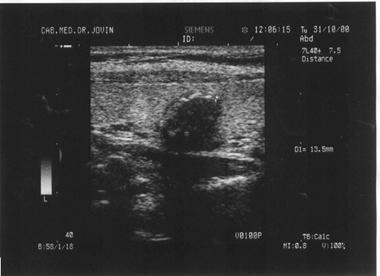

Imaginea hiperecogena

Atunci cand reflectarea ultrasunetelor este foarte intensa, pe ecran nuantele de culoare vor fi aproape de alb. Exprimarea semiologica va fi corespunzatoare unei structuri accentuat ecogene sau hiperecogene. Imaginea hiperecogena este data de bogatia continutului in tesut fibros, conjunctiv si grasime a structurii respective.

Exemple:

structuri dense, dure, impenetrabile pentru fasciculul ultrasonor care va fi in intregime reflectat (calculi);

steatoza hepatica;

hemangiomul hepatic

Figura 5. Hemangiom hepatic lobul stang

Figura 6. Hemangiom renal - la nivelul treimii medii a

rinichiului drept, mica zona hiperecogena, rotunda, care deformeaza conturul

renal.

Figura 7. Litiaza biliara

Figura 8. Litiaza coledociana